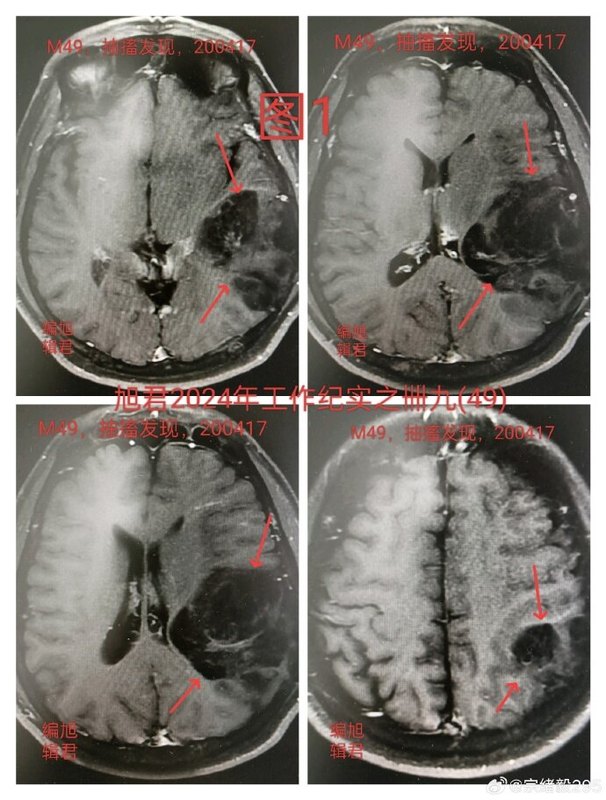

一位49歲患者,因右上肢抽搐就診,經(jīng)CT和MRI檢查發(fā)現(xiàn)左顳頂枕部存在巨大占位性病變,見下【圖1-3】。經(jīng)評(píng)估后決定行手術(shù)切除。一、手術(shù)過程:術(shù)中發(fā)現(xiàn),腫瘤部分區(qū)域邊界清晰,但大部分與正常腦組織界限不清,且血供豐富。為在最大限度保護(hù)功能的前提下盡可能完整切除腫瘤,手術(shù)沿腫瘤邊界,適當(dāng)擴(kuò)大切除范圍,并通過吸引器判斷組織特性,精準(zhǔn)控制切除深度(外科醫(yī)師的觸覺判斷在此過程中至關(guān)重要)。二、術(shù)后治療與隨訪:術(shù)后病理確診為星形細(xì)胞瘤II級(jí),隨后接受放療,未行化療。術(shù)后前三個(gè)月定期復(fù)查,隨后改為每半年復(fù)查,四年來病情穩(wěn)定,未見腫瘤復(fù)發(fā)。最近的影像學(xué)復(fù)查結(jié)果依然良好,見下【圖-4】。三、關(guān)于膠質(zhì)瘤的治療思考:經(jīng)過數(shù)十年的臨床研究,膠質(zhì)瘤的治療仍以盡可能徹底的手術(shù)切除為核心。完整切除是決定預(yù)后的關(guān)鍵因素。然而,外科醫(yī)師對(duì)腫瘤與正常腦組織的界限判斷、對(duì)手術(shù)器械的精準(zhǔn)操控以及操作時(shí)的觸覺感知,都會(huì)直接影響切除的完整性和患者的長期生存預(yù)后。本病例正是通過精準(zhǔn)切除,結(jié)合術(shù)后放療,實(shí)現(xiàn)了四年無復(fù)發(fā)的良好結(jié)果,印證了精準(zhǔn)外科在膠質(zhì)瘤治療中的核心價(jià)值。祝?;颊呓】甸L存,遠(yuǎn)離復(fù)發(fā)!